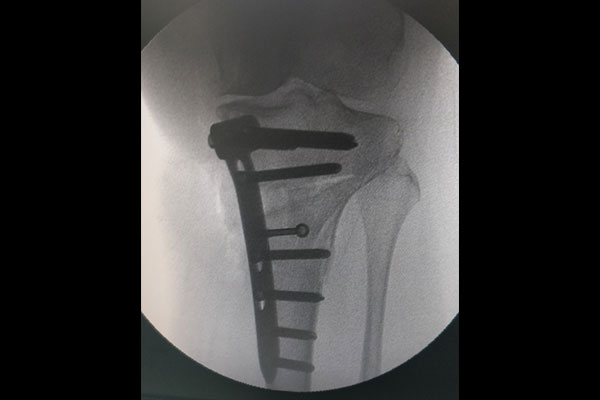

STEPS OF HTO